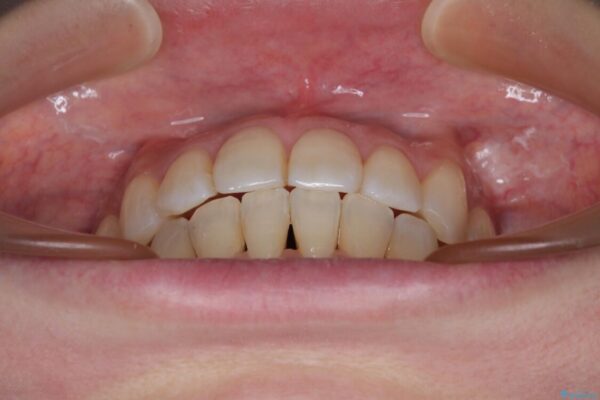

治療後について

歯の傾斜が改善され、インプラントによるクラウンが装着されたことで、物が挟まることもなくなりました。

治療後

• インビザラインによる矯正治療と奥歯のインプラント治療 治療後画像